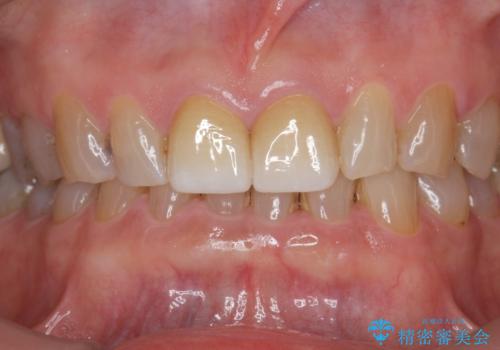

ディープバイト・噛み合わせが強いことからフルジルコニアクラウンを選択しました。

- 17.6万円(仮歯・フルジルコニアクラウン)費用は治療当時の料金となります

フルジルコニアクラウンは全てジルコニアで生成されたセラミッククラウンで、前歯の噛み合わせが強い場合に切端の欠けを防ぎます。